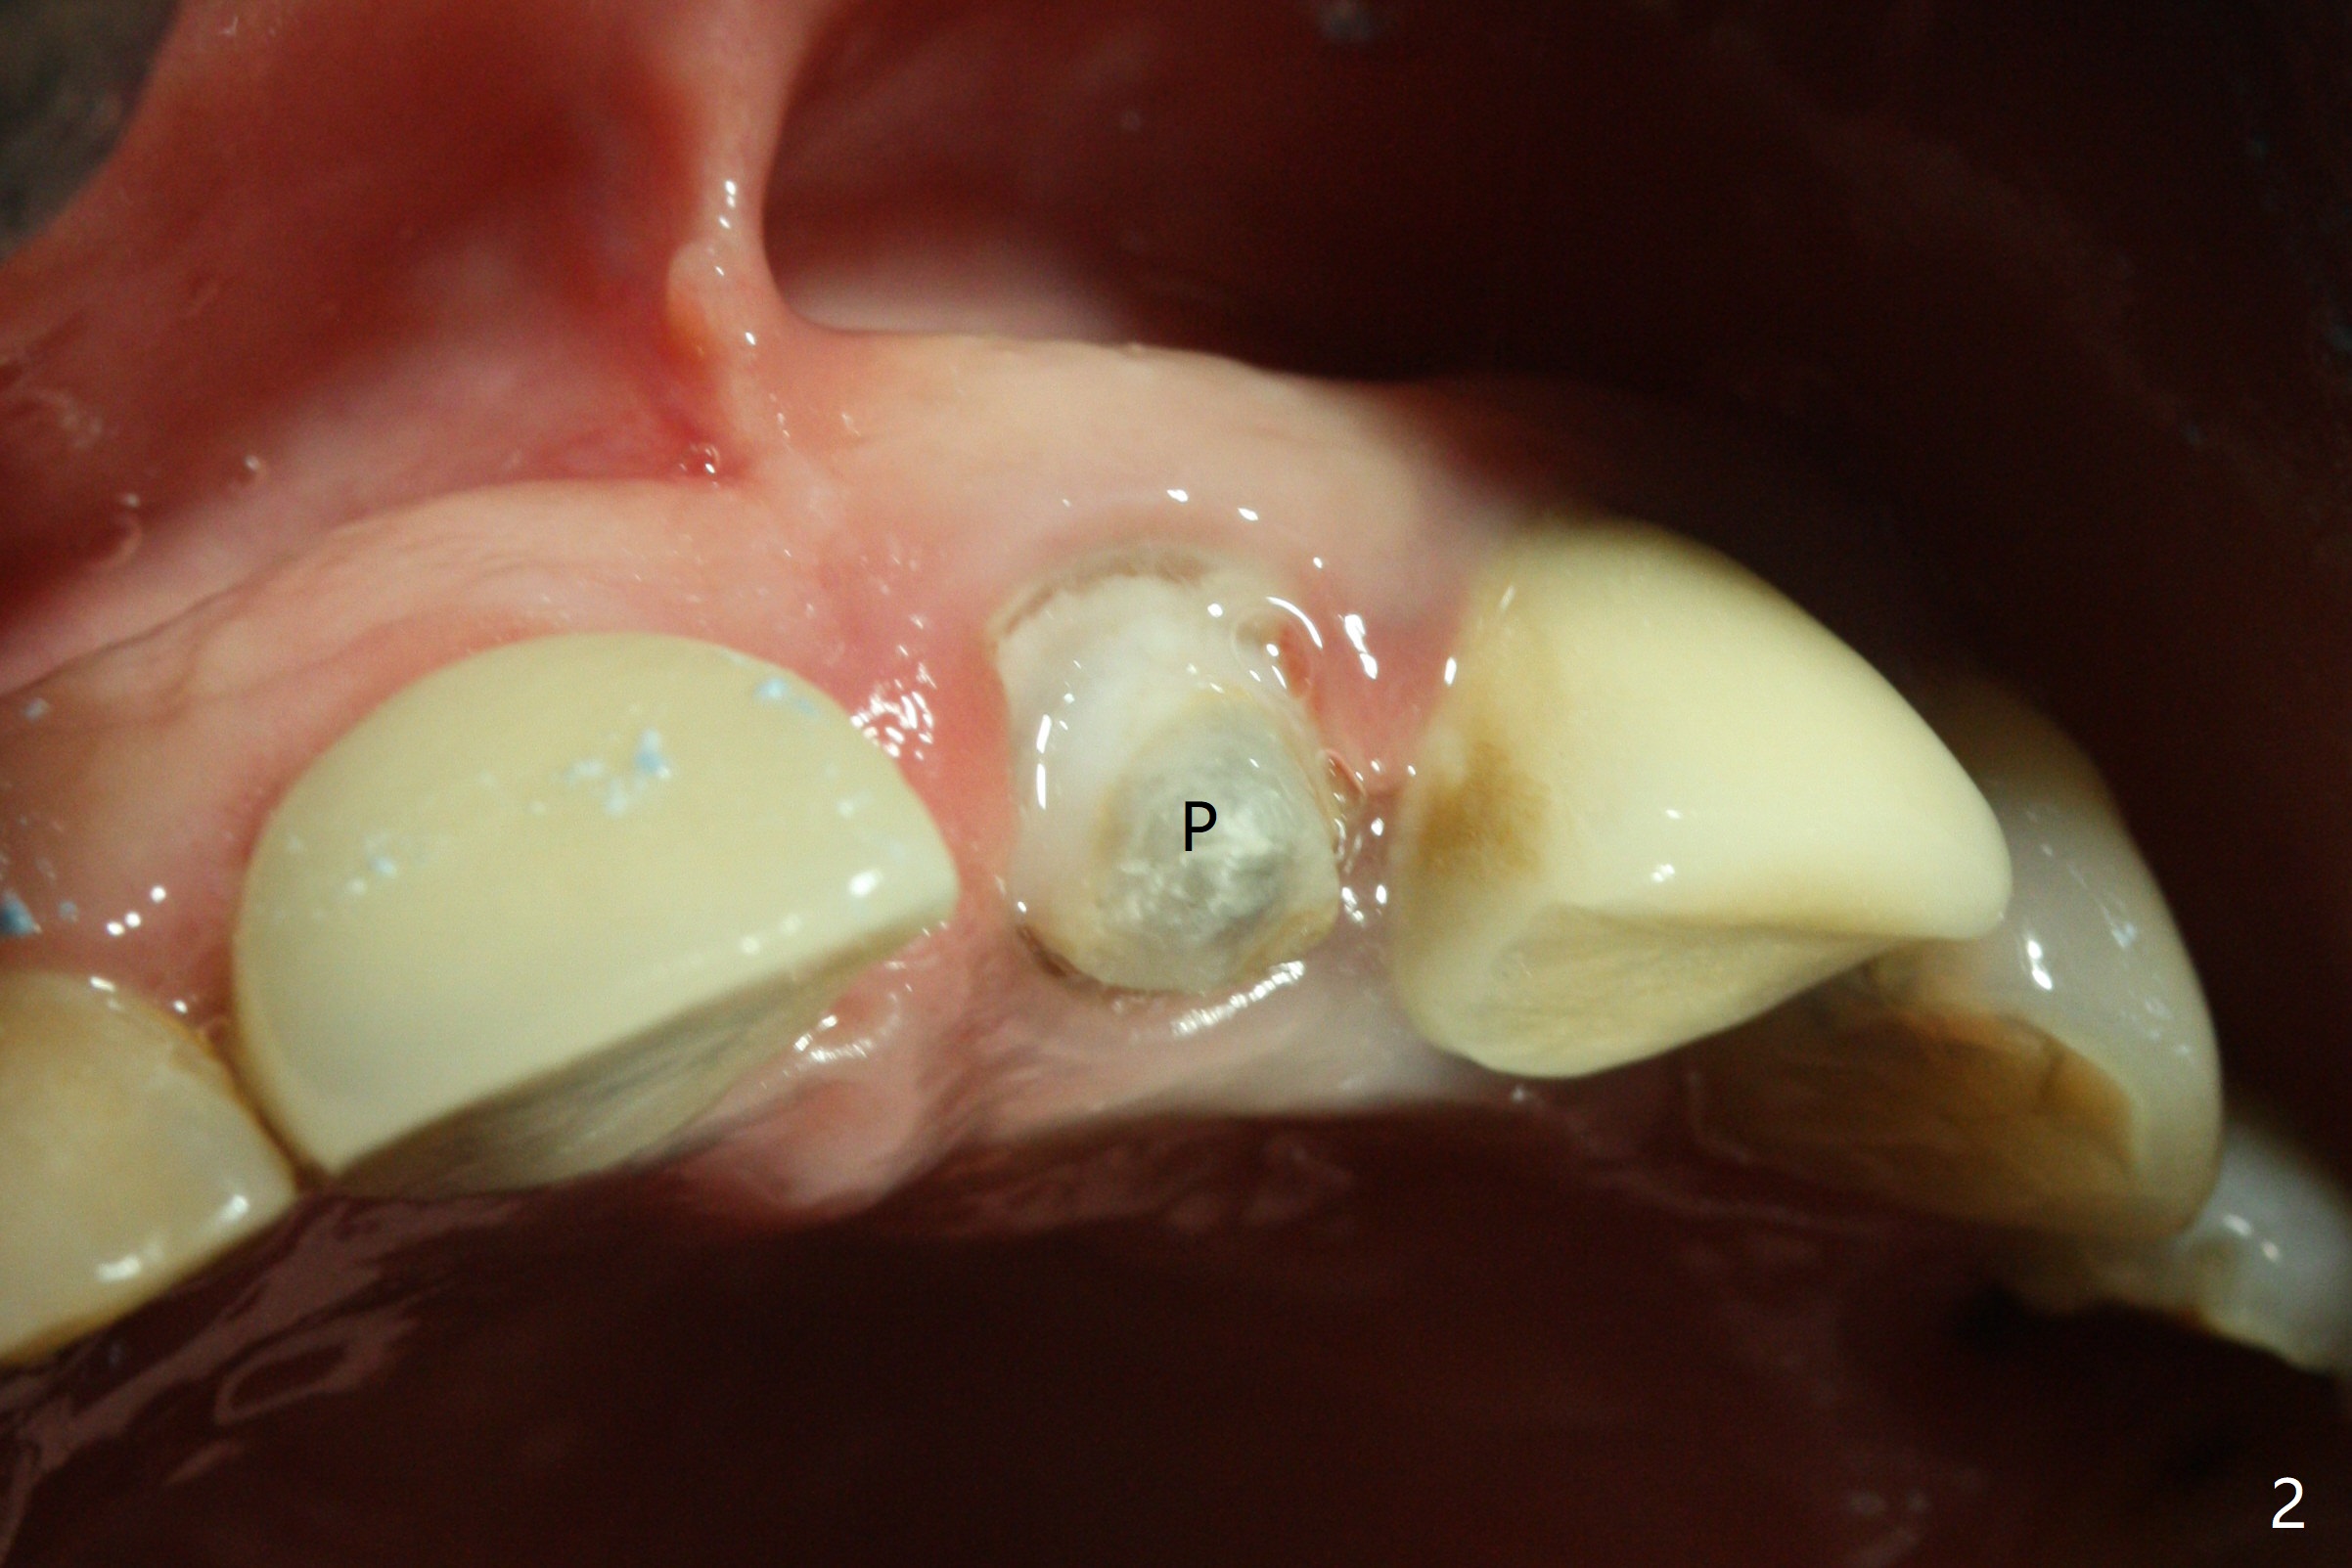

When the 44-year-old woman returns, the crown dislodges from #9 with palatal porcelain chip (Fig.1). Although the post is in place as compared to its dislodgement last visit, it is short and pointed (Fig.2,3 P). Because of the anterior deep bite (Fig.4), an implant restoration may not provide advantage; a new build-up is fabricated (B-U) for a new crown (Fig.5-6). The existing crown is reinserted for shade comparison (Fig.7 C). The gingiva at #8 and 9 is healthy, whereas that at #10 is not (Fig.8). PA taken 5 months later shows that the crown at #10 looks normal (Fig.9).